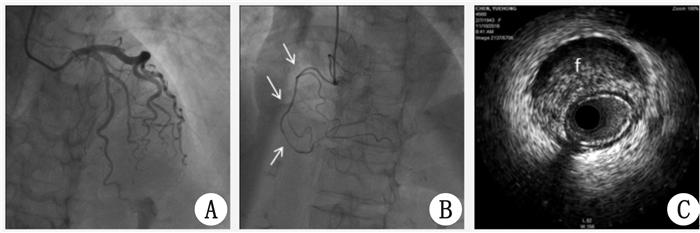

病例2 患者,女,73岁,因“反复胸痛2 d,心肺复苏术后1 d”于2016年11月5日入院。2016年11月3日行走时突发心前区隐痛,持续2 min,伴头晕,反复发作多次,2016年11月4日当地医院心电图:窦性心律左前分支传导阻滞,予以急诊留观输液时突发意识不清,心电监护提示室颤,予以双相波200 J除颤心肺复苏后患者意识恢复,心律转为窦性,后转本院。高血压病病史20余年,血压控制可。入院查体:BP124/83 mmHg,神清,两肺呼吸音粗,心率73次/min,律齐,心瓣膜区未闻及病理性杂音。CK-MB 22 U/L,肌钙蛋白TNI 1.563 pg/mL,B型尿纳肽(前体)(NT-PROBNP)288 pg/mL(参考值0~450)。心超:未见明显室壁节段性运动异常,左室射血分数(LVEF)63%;心电图:Ⅱ、Ⅲ、aVF病理性Q波。诊断:心肺复苏术后,急性心肌梗死,高血压病。给予阿司匹林、氯吡格雷、阿托伐他汀、美托洛尔片、厄贝沙坦片、低分子肝素针等治疗,病情稳定。2016年11月10日冠脉造影显示:右冠全程及左室后支、后降支弥漫性重度狭窄(图 3A、B)。右冠IVUS显示:右冠全程夹层及壁间血肿、官腔重度狭窄(图 3C)。术后继续药物治疗。住院观察12d,无胸痛再发,心电监护未见恶性心律失常。

| 图 3 病例2冠脉造影及IVUS:白色箭头示右冠自发性夹层,f示假腔 |